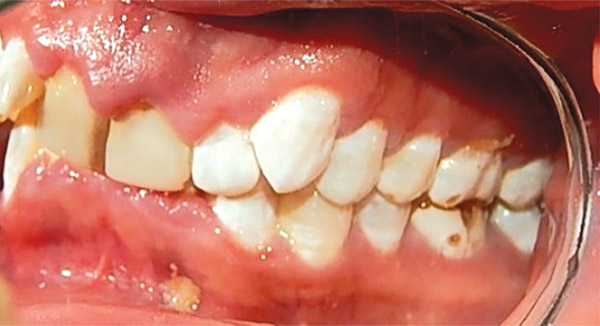

Figura 3. Intraoral derecha.

En las fotografías intraorales se muestra la fluorosis dental Tf4 y Tf7, las relaciones molares clase II molar y canina bilateral (Figura 3 y 4), el apiñamiento severo superior e inferior, con el órgano dental 35 en infraoclusión. El overbite aumentado y las líneas medias dentales no son coincidentes (Figura 5), las formas de arco superior e inferior son cuadradas (Figura 6 y 7).